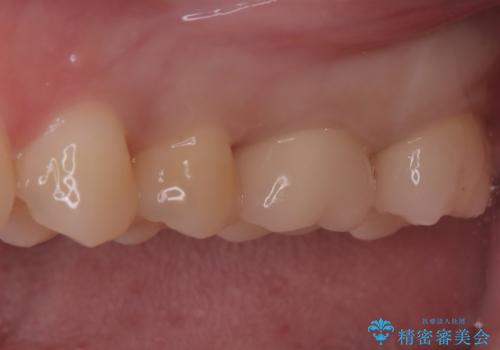

セラミックによる修復: 最終的な被せ物(または詰め物)にはセラミックを使用しました。高い適合性により、二次的な虫歯のリスクを抑えつつ、天然歯のような自然な咬み心地と美しさを再現しました。